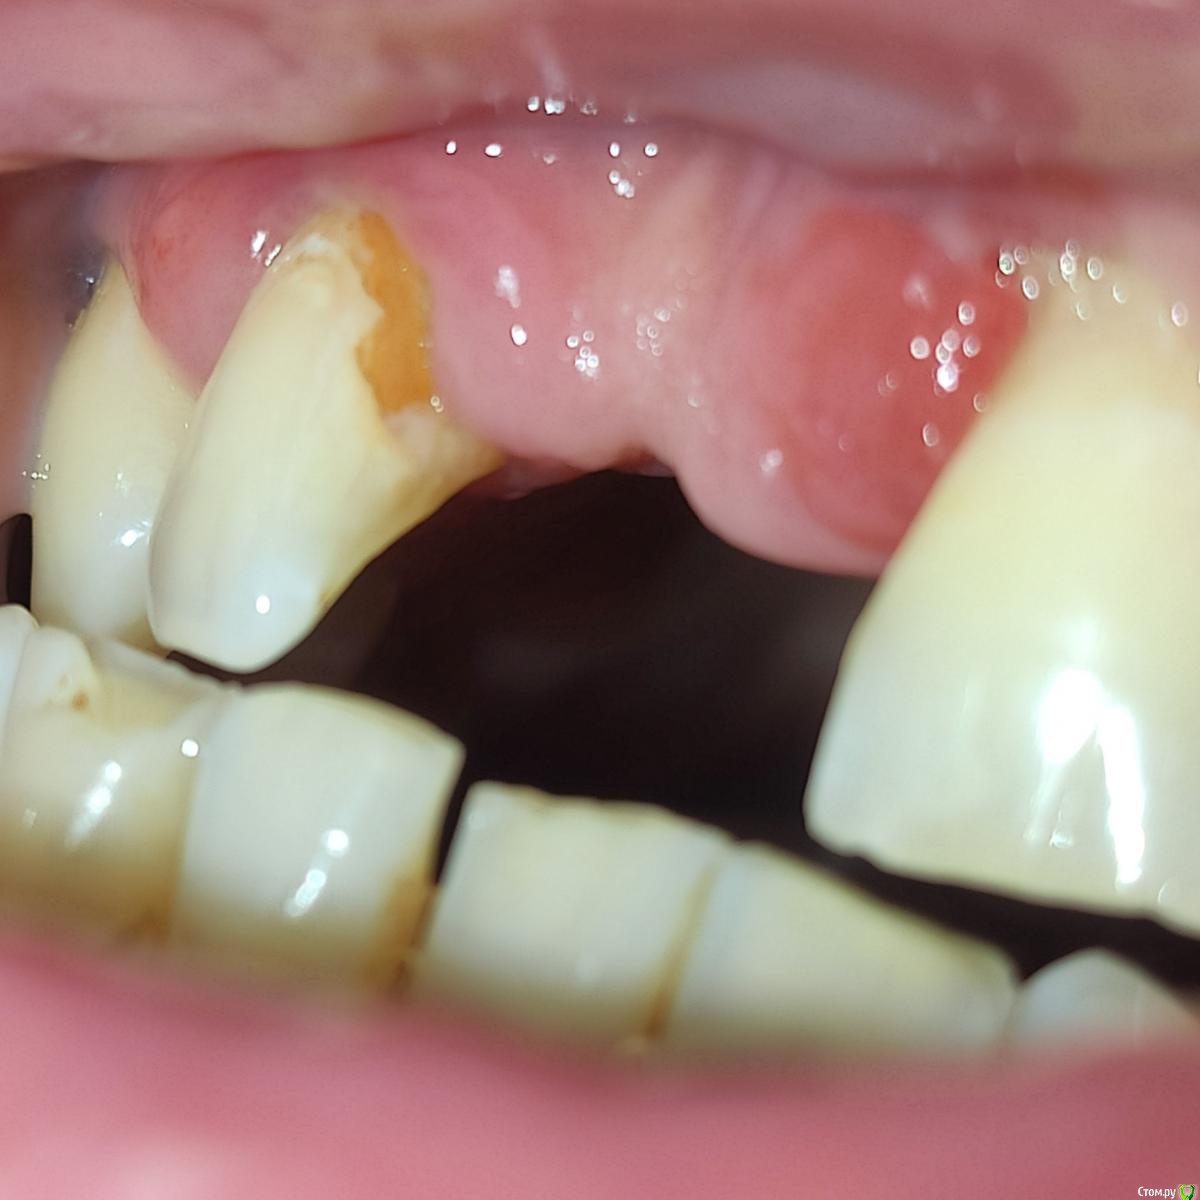

Bier Опубликовано 31 января, 2020 Поделиться Опубликовано 31 января, 2020 после удаления какие варианты лечения? надо же кость наращивать?смотря какие требования по эстетике. Нужны фотографии, КТ Ссылка на комментарий

red_butler Опубликовано 31 января, 2020 Поделиться Опубликовано 31 января, 2020 по эстетике никаких требований, главное долговечность и чтобы кость дальше не уходилапокажите фото, что бы было видно зубы и десну. и сделайте Кт Ссылка на комментарий

andrewV Опубликовано 3 марта, 2020 Автор Поделиться Опубликовано 3 марта, 2020 (изменено) В одной из клиник предложили удалить единичку с кистой и обточить двойки под коронки, на них же можно будет повесть временный протез, пока будут приживаться импланты и костная ткань. Можно ли как-то обойтись без обточки, но не ходить 3-4 месяца без передних зубов? Почему-то ничего не сказали насчет кариеса корня на двойке, его же надо депульпировать в таком состоянии? Изменено 3 марта, 2020 пользователем andrewV Ссылка на комментарий

DmitrySH Опубликовано 3 марта, 2020 Поделиться Опубликовано 3 марта, 2020 но не ходить 3-4 месяца без передних зубов? Съемный протез, если он возможен при проведении костной пластики в вашей ситуации. Почему-то ничего не сказали насчет кариеса корня на двойке, его же надо депульпировать в таком состоянии? Его надо избавить от кариеса и действовать по ситуации. Ссылка на комментарий